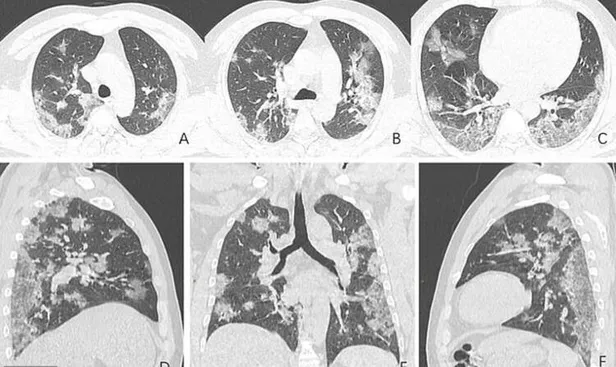

Kuzey Amerika Radyoloji Topluluğu, corona virüsü nedeniyle hayatını kaybeden 44 yaşındaki Çinli bir hastanın röntgen görüntülerini web sitesinde yayınladı.

Kuzey Amerika Radyoloji Derneği tarafından yayınlanan taramalar, A görüntüsünden F görüntüsüne ulaşana kadar hastanın akciğerlerindeki sıvının, zaman içinde açıkça nasıl daha belirgin hale geldiğini gösteriyor.